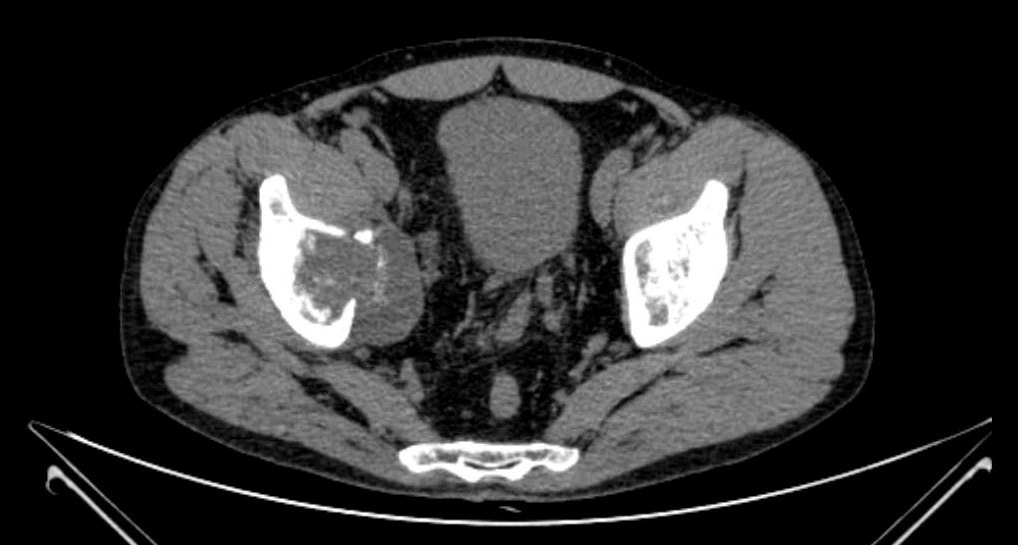

Фото: КТхондросаркома вертлужной впадины правой подвздошной кости

Выполнение лишь одного метода визуализации не позволяет достаточно оценить данную патологию, например, рентгенография и компьютерная томография позволяют детально оценить изменение костной ткани, однако из-за специфики оптических свойств не дают полного представления о мягкотканных структурах и распространении по костномозговому каналу, что требует выполнения магнитно-резонансной томографии. Оценить распространение заболевания в целом позволяет применение различных методов радионуклидной диагностики – остеосцинтиграфии, ОФЭКТ и ПЭТ компьютерной томографии.

Диагностика данной патологии состоит из нескольких этапов. Первым является сбор анамнеза и истории заболевания при клиническом осмотре онколога. Затем выполнение различных лучевых методов визуализации: рентгенографии, ультразвукового исследования, компьютерной и магнитно-резонансной томографии, сцинтиграфии, а иногда и протонно-эмиссионной томографии.